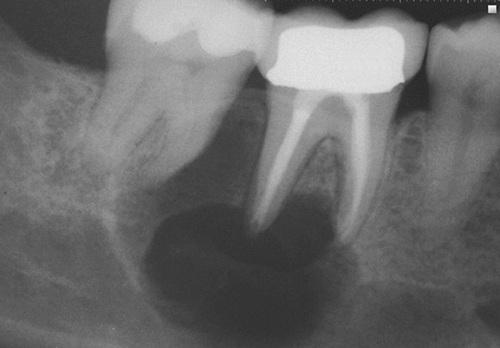

Clinical Features

- encountered most often in older patients (60 years)

- twice as common in men as in women

- pain and swelling are common complaints

Radiographic Features

- may mimic those of any odontogenic cyst

- radiolucent defect with irregular, ragged margins

Radiolucent lesion with irregular, ragged margins surrounding the crown of an impacted third molar in a 56-year-old woman. This was clinically considered to be a dentigerous cyst.

odontogenic carcinoma